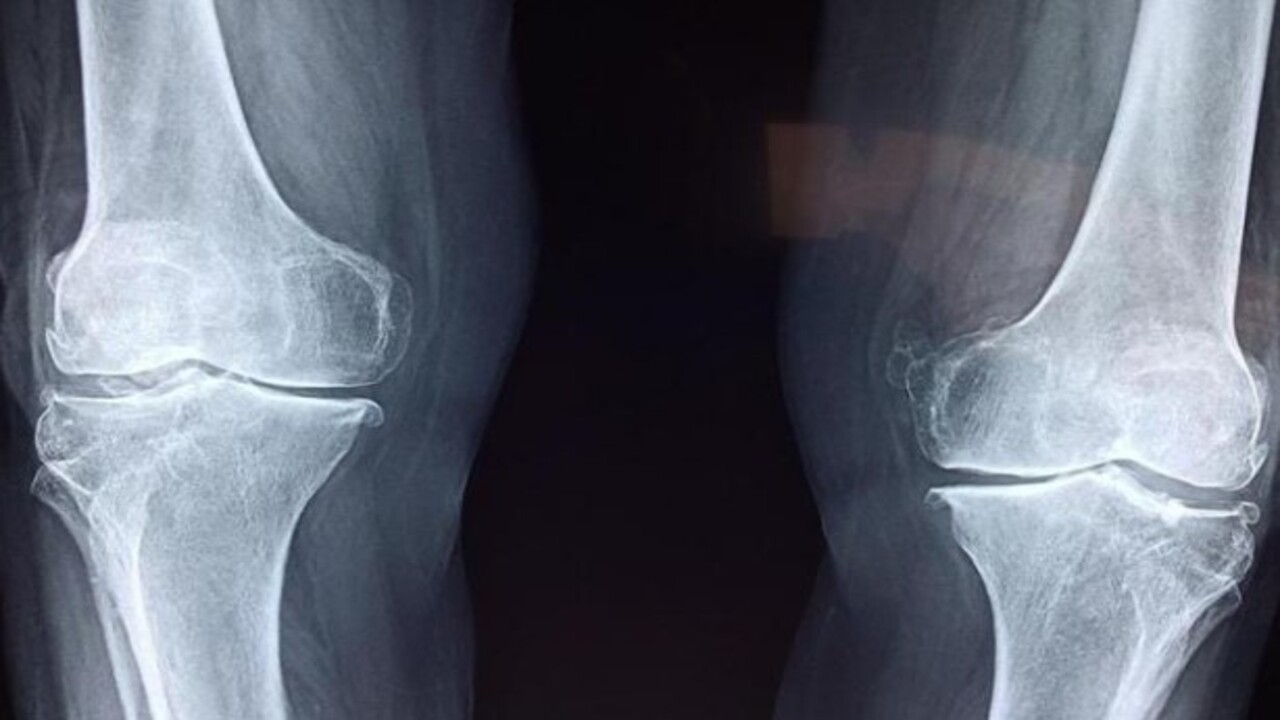

Deneyenler şaştı kaldı! Eklem ağrısından kurtulmanın yolu bakın neymiş

Sizlere yalnızca basit bir alüminyum folyo yardımıyla eklem ağrılarından nasıl kurtulabileceğinizi anlatacağız. Alüminyum folyonun şifalı gücü, düşündüğünüzden bile fazla olabilir... Eklem ağrılarını alüminyum folyo ile tedavi etme yöntemi, en ucuz ve en etkili yollardan biridir!

Alüminyum Folyo ile Tedavi Her şeyden önce, alüminyum folyo ile tedavi yöntemini detaylı şekilde açıklayan psikolog doktor Wilhelm Reich'e teşekkür etmek gerekir. Alüminyum folyo yardımıyla soğuk algınlığı, siyatik, boyun kireçlenmesi ve gut hastalığı gibi rahatsızlıklar bile tedavi edilebilmektedir.